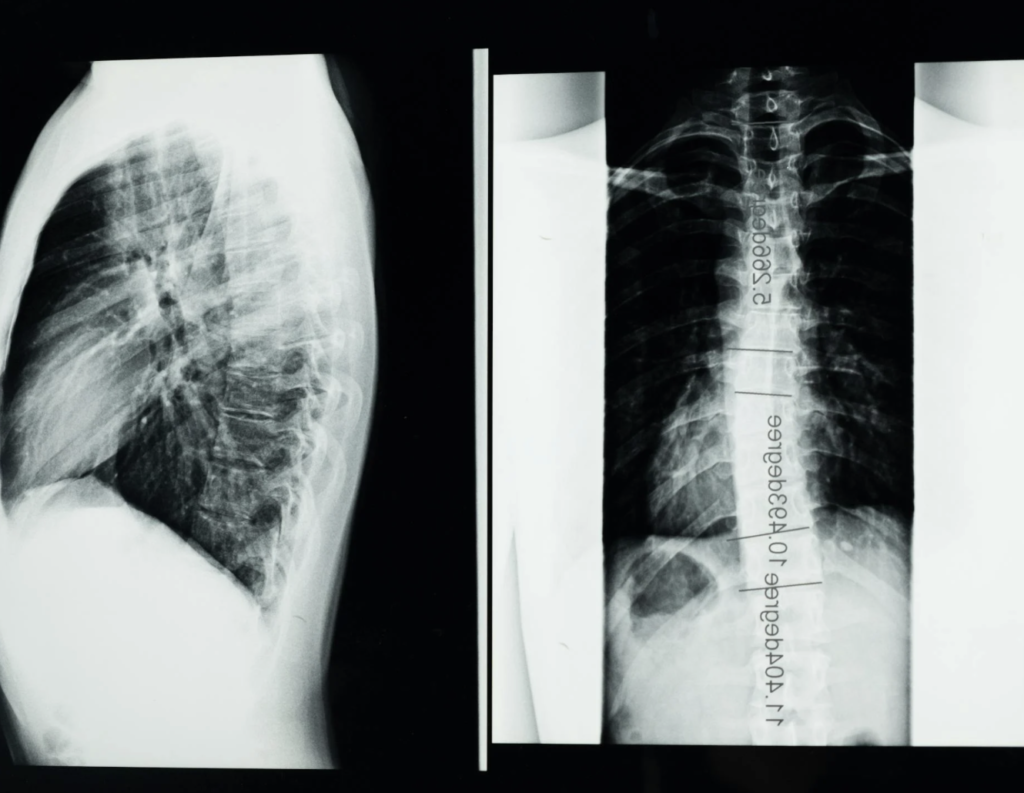

Skoliosis dapat diartikan secara sederhana sebagai suatu kondisi kelainan pada tulang belakang (spine) yang ditandai dengan lengkungan tidak wajar yang bisa membentuk huruf “C” atau “S”.

Menurut sumber ilmiah, skoliosis berarti kondisi tulang belakang yang menunjukkan derajat lengkungan yang melebihi 10 derajat ketika diukur menggunakan metode Cobb angle pada radiografi. Kelengkungan ini dapat terjadi di daerah dada (thorax), pinggang (lumbar), atau keduanya.

Derajat Keparahan Skoliosis

Keparahan skoliosis bisa dikategorikan dalam 3 level. Yang pertama ialah ringan, dengan sudut Cobb 10-25 derajat. Lalu level sedang dengan sudut Cobb 25-40 derajat. Terakhir level berat dengan sudut Cobb lebih dari 40 derajat.